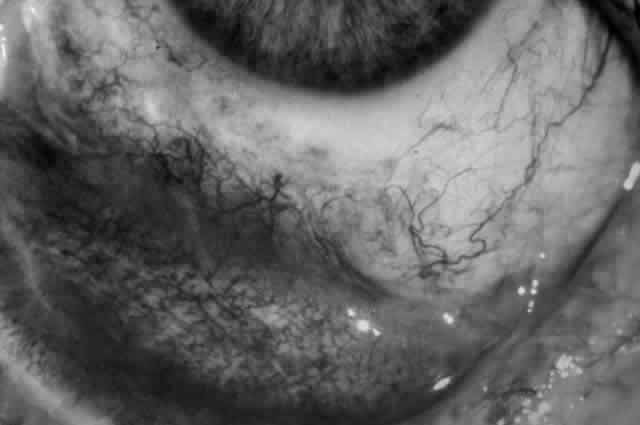

The conjunctival involvement in pemphigus may lead to symblepharon as a result of the formation and rupture of small vesicles. This does not, however, lead to progressive scarring and blindness, as is so often the case in cicatricial pemphigoid (Fig. 4).13